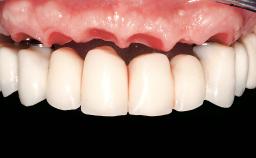

Immediate Loading of Six Implants in the Maxilla and Final Restoration with a Full-Arch Gold/Ceramic FDP Involving the Concept of Tilted Implants

A 61-year-old male patient with a failing fixed maxillary rehabilitation and a fixed mandibular rehabilitation requested a new fixed maxillary rehabilitation. The patient was wearing a temporary metal-reinforced maxillary bridge inserted two years before the consultation. He reported that his previous dentist did not want to insert a definitive framework because he considered the residual teeth to have a negative prognosis. The patient reported a history of recurrent caries and endodontic complications as the main reason for the previous extractions. The anamnesis was negative for periodontal disease and bruxism. The patient’s chief compliant was the mobility of his maxillary prosthesis, which needed to be re-cemented frequently, and discomfort during chewing.Moreover, the patient was not satisfied with the esthetic appearance of his maxillary teeth, which he found too long. The patient asked for a stable and comfortable fixed maxillary rehabilitation and firmly rejected any removable solution.